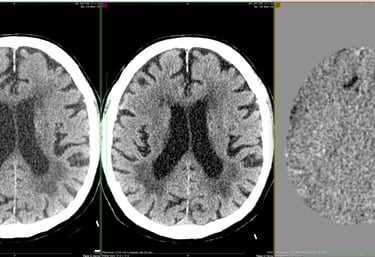

Images consisting of new, 6 month prior and subtraction imaging of the same plane in a patient with multiple falls. Other images showed a left parietal interval stroke. The right frontal interval stroke is easy to mischaracterize as a sulcus, but changes the expected source of underlying emboli from the left ICA to the heart or aorta, changing the diagnostic workup.